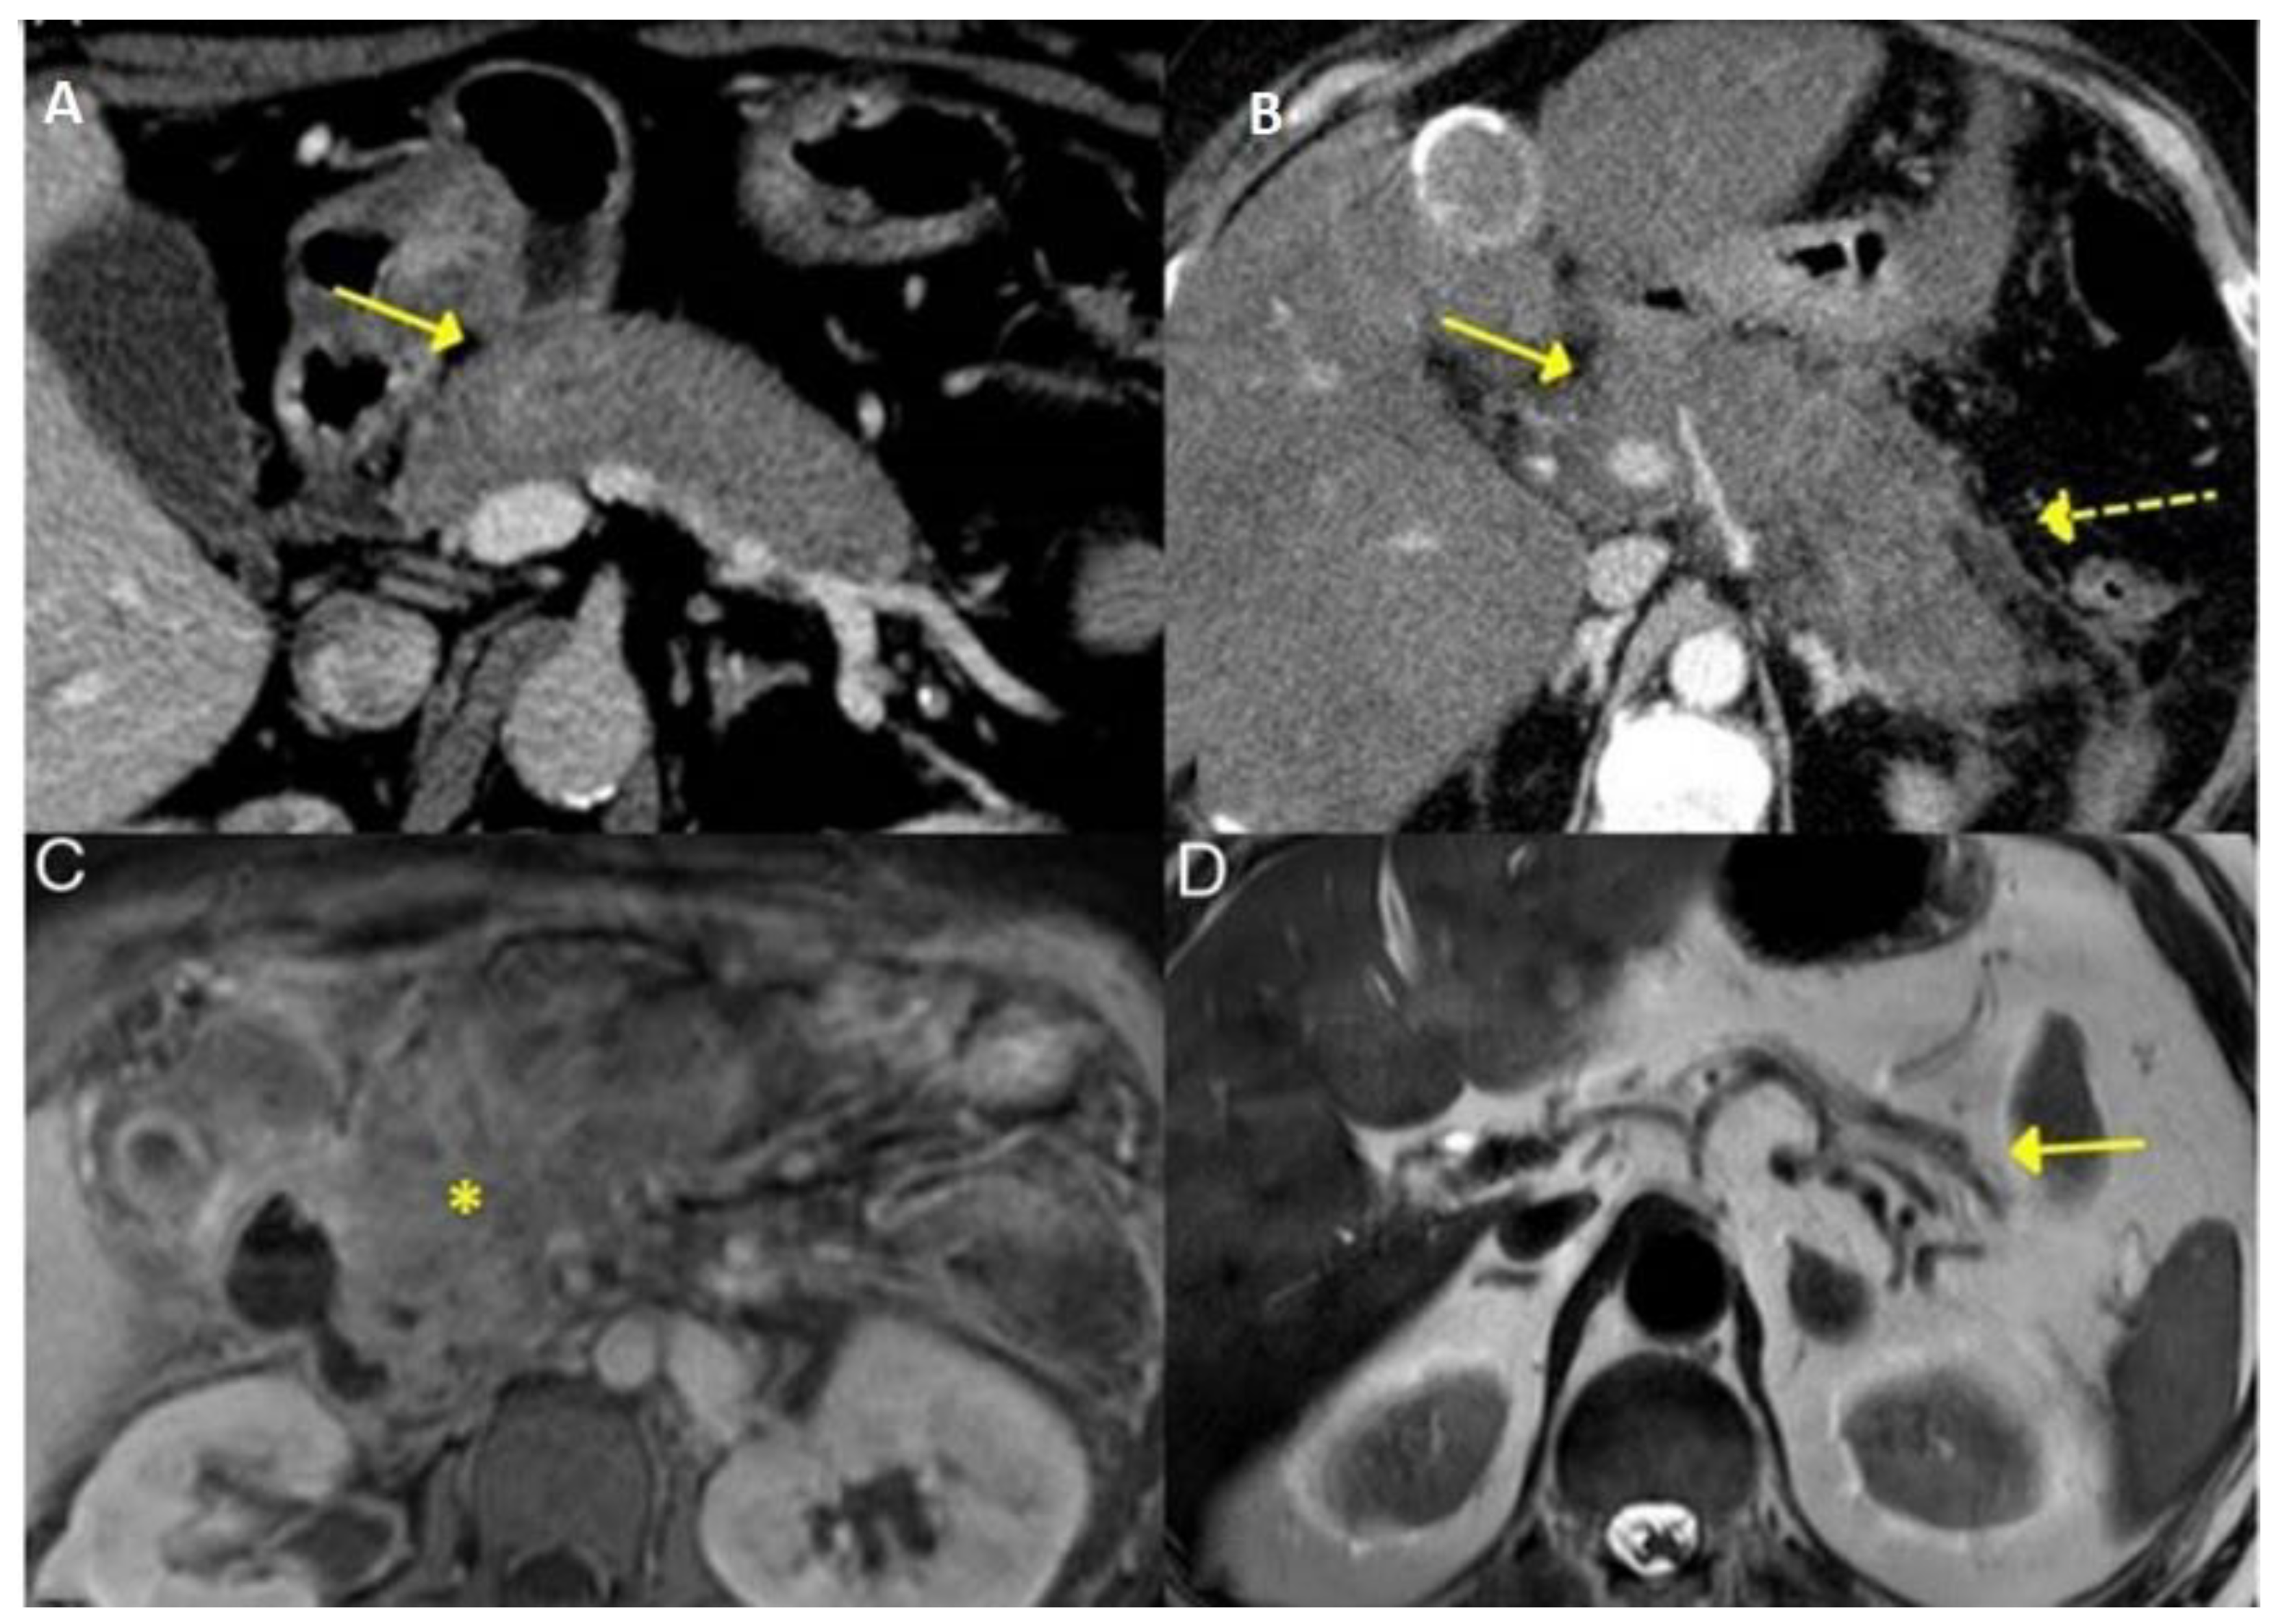

3.2.4. Liver and Bile Ducts